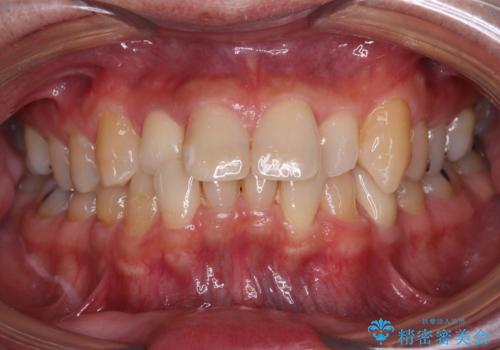

- 内側に倒れている前歯が擦れてしみるとのことで来院された患者様です。

削れていた部分は詰め物が入っていましたが、縁の部分がしみているようで、変色も目立っていたため、オールセラミッククラウンにて補綴治療を行うこととしました。

内側に倒れているため、下顎と強く干渉することが懸念されましたが、無理のない咬み合わせで、形態も左右対称に近い状態で仕上げることができました。